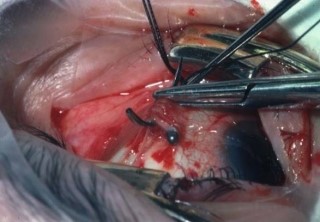

1.peritomy

eye speculum 으로 벌린 후 tooth + wescott's scs로 cunjuctive 를 분리

2.Insertion of squint hook under rectus muscle , insertion of bridel suture

cornea cover 올려 놓은 후

3-0black silk + SB Kit 내의 muscle hook(가장 큰것) 으로 걸고 tagging suture -

->교수님께서 기본 set내의 scs로 cut 하고 mosq tagging은 안하고 실의 끝부분을 묶어 놓음

->needle의 끝부분에 물어서 뒤로 back 으로 suture 함(needle 뾰족한 부분을 holding)

4군데 rectus muscle을 tagging suture 다함

Assist는 주걱모양의 Retractor

4. cryopexy

while vieweing with indirect opthamocope indirect sclera gently with tip of cryoprobe

->freeze break until sensory retina just turns white

4. Encircling procedure

5-0 ethibond 로 suture (cvd needle)

->suture한 부위에 silicone tube 506의 끝을 뾰족하게 scs로 자른 후 넣는다.

(미리 silicone tube 506은 GM bss 용액에 담아 놓는다)

->SB Set내에 있는 ㄱ자 fcp으로 insertion

->cut scs: wescott , retractor: 주걱모양

assist 의 손이 부족 하기 때문에 주걱모양 retractor 사용시 도움이 필요

교수님께서 suture할 때 black silk 당긴 채 suture